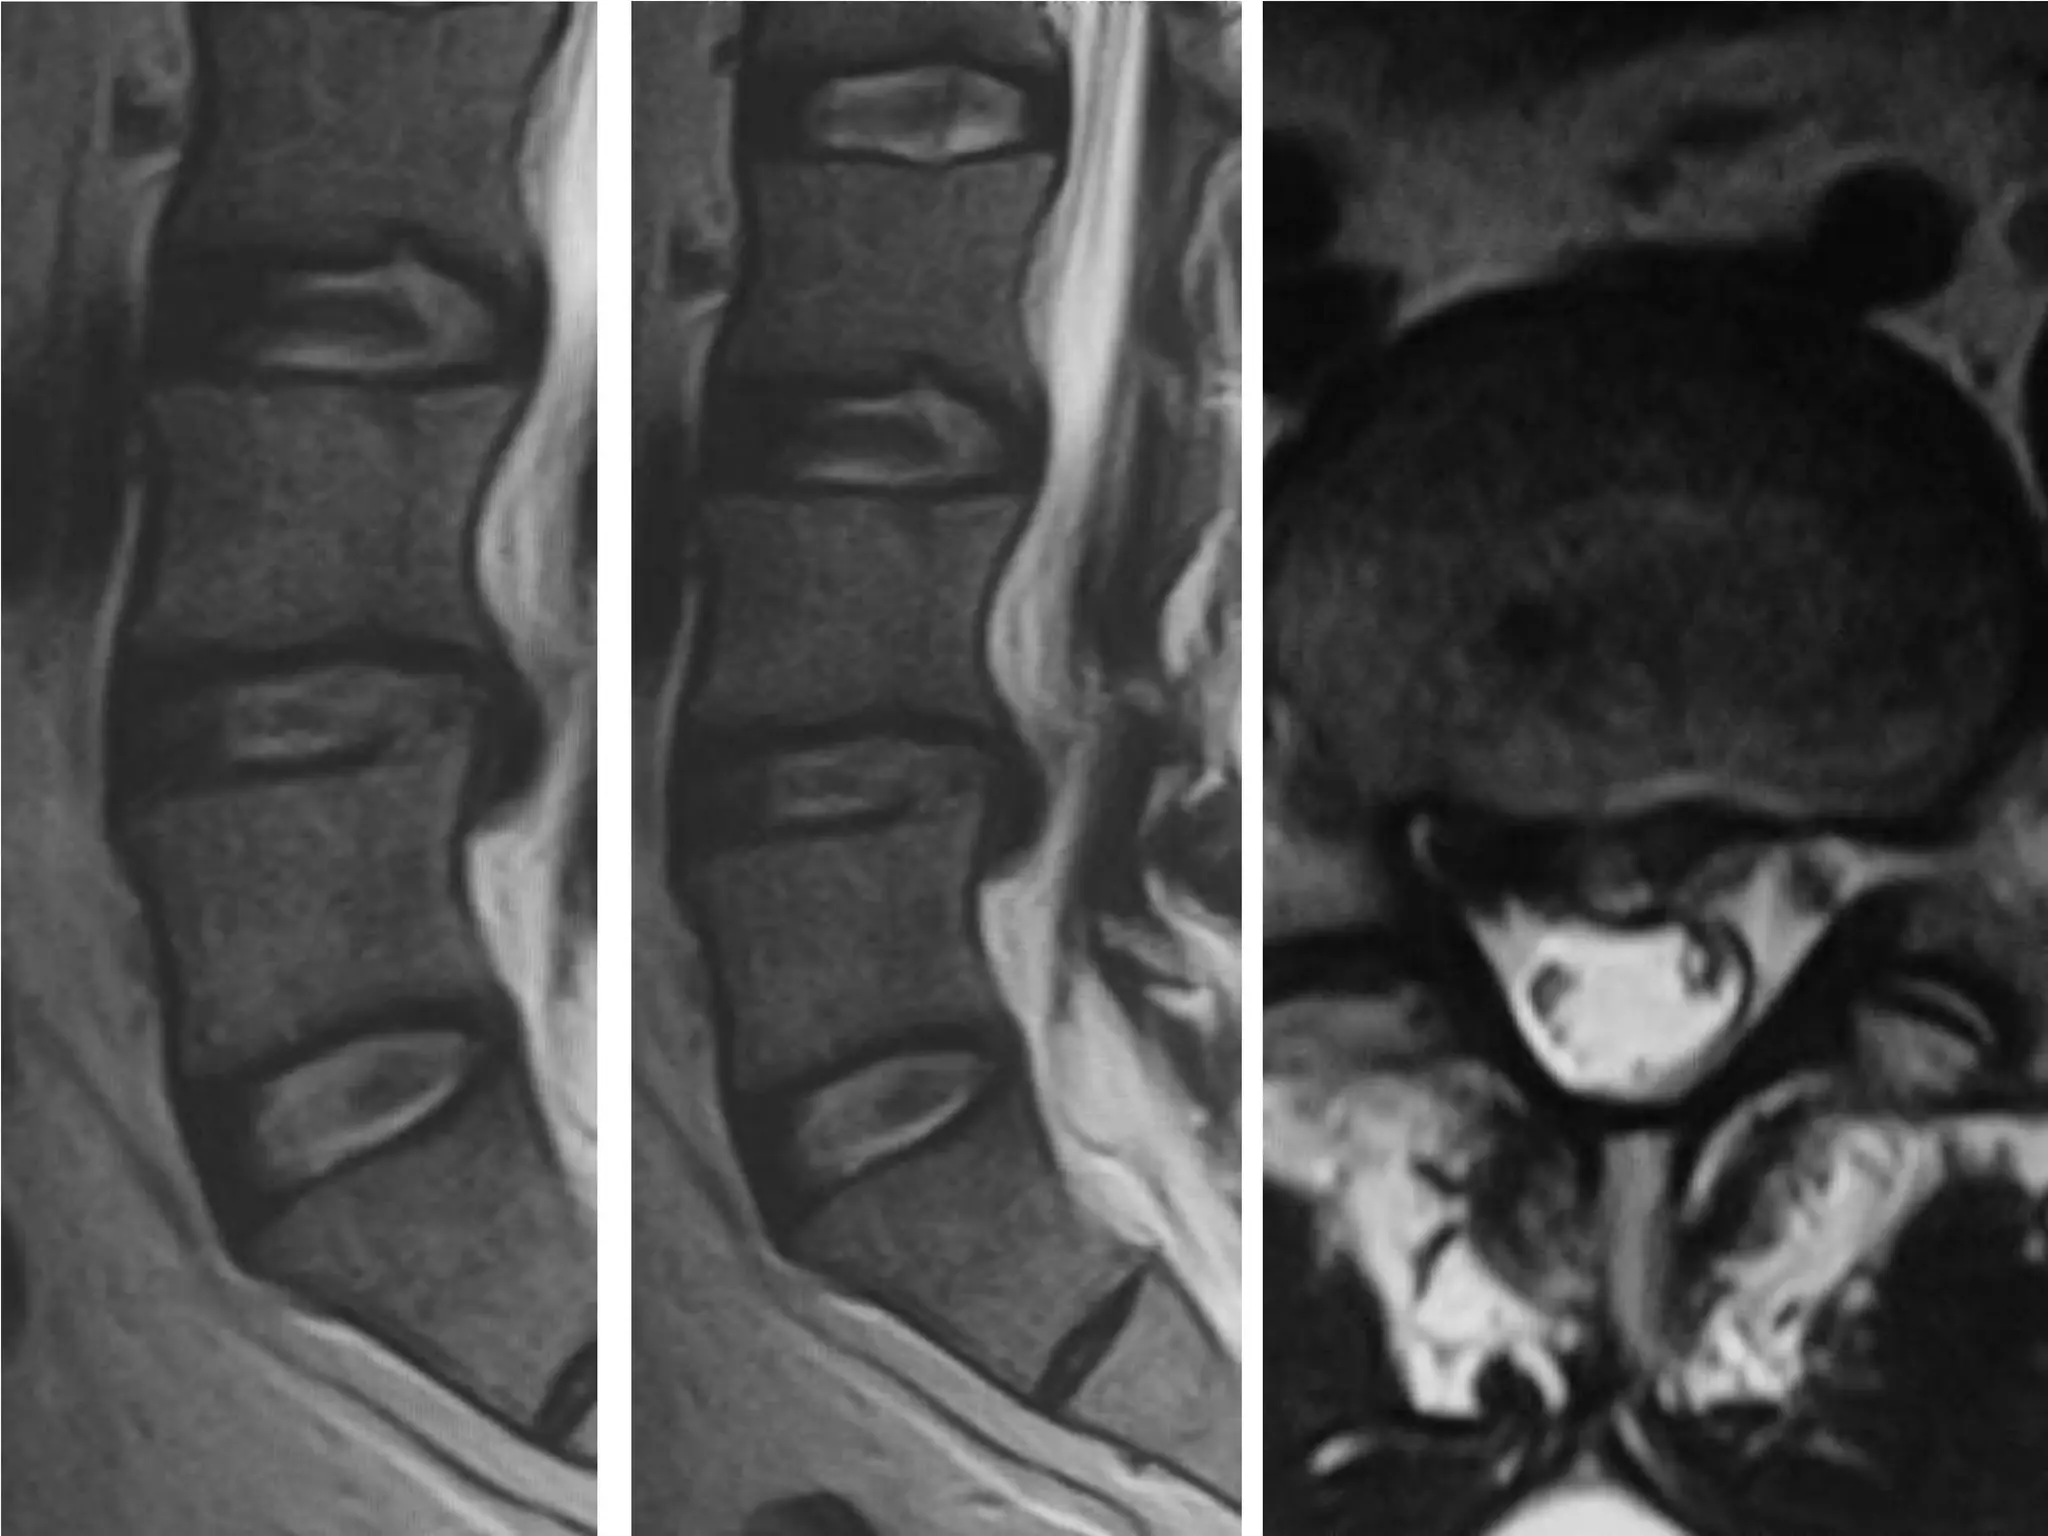

Dynamic Degenerative InstabilityFlexionExtension

Cervical Degenerative Listhesis